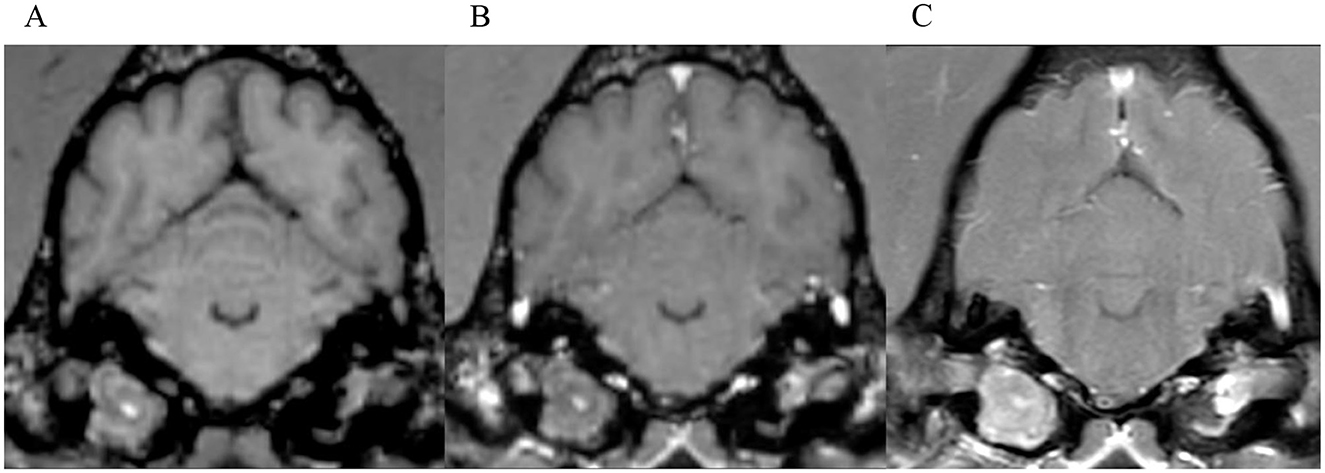

Results on grading of mass effect, distribution and pattern of ME, cochlear enhancement and categorization of cases can be found in supplementary Tables 3, 4. Examples of moderate and marked meningeal enhancement can be seen in Figures 9, 6, respectively.

Figure 9. Transverse images at the level of the tympanic bullae. Example of a case with moderate meningeal enhancement in a dog, interpreted by observer 1. (A) is the T1W-pre-contrast image, (B) the 3D-GRE-T1W and (C) the FS-TSE-T1W.